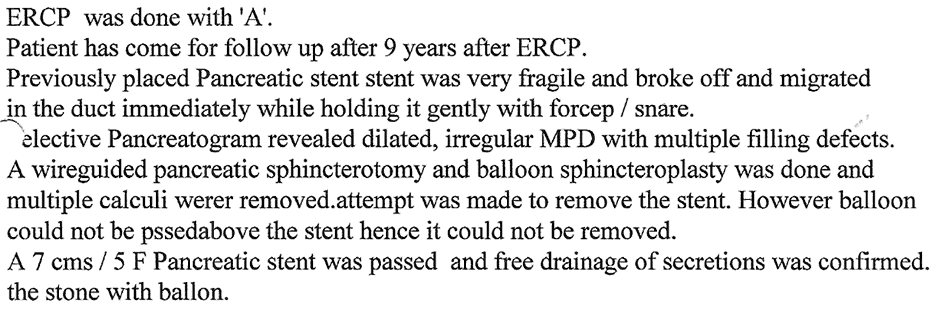

Chronic Pancreatitis is condition which can result in recurrent attacks of persistent and severe pain.

This can be due to presence of stones or narrowing of the pancreatic duct and can be treated by ERCP.

Treatment of Chronic Pancreatitis by Stent

Most of the lesions of biliary system and pancreas were treated earlier by surgery with its own complications, but now with ERCP these conditions can be treated without any surgery and morbidity and mortality related to surgery, and as a cheaper option for surgery and has become treatment of choice for the same.